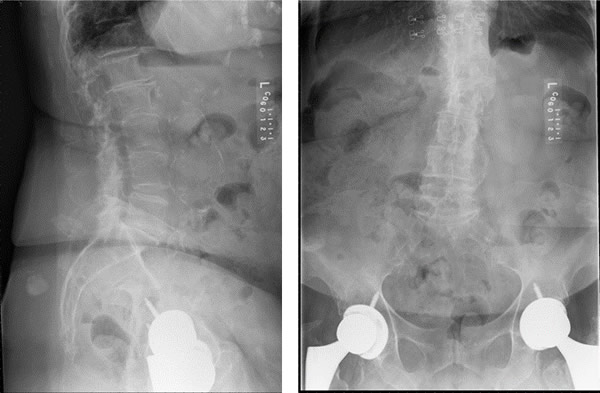

But recently, pain in her back reached a new level. That's when she found Columbia Orthopaedic Group pain specialist, Dr. J. Camp Newton.

Recently, Dr. Newton performed Radiofrequency Ablation on Glenda which is a burning of the nerves that are causing the pain.

Dr. Newton is a fellowship-trained Interventional Pain physician and provides a comprehensive multi-modal pain management program. This begins with a detailed diagnostic workup that includes clinical evaluation and necessary studies and imaging. After evaluation, he initiates conservative adjunctive medical management and appropriate interventional therapy. He also implements functional restorative programs such as physical therapy and cognitive/behavioral evaluations and treatment programs.